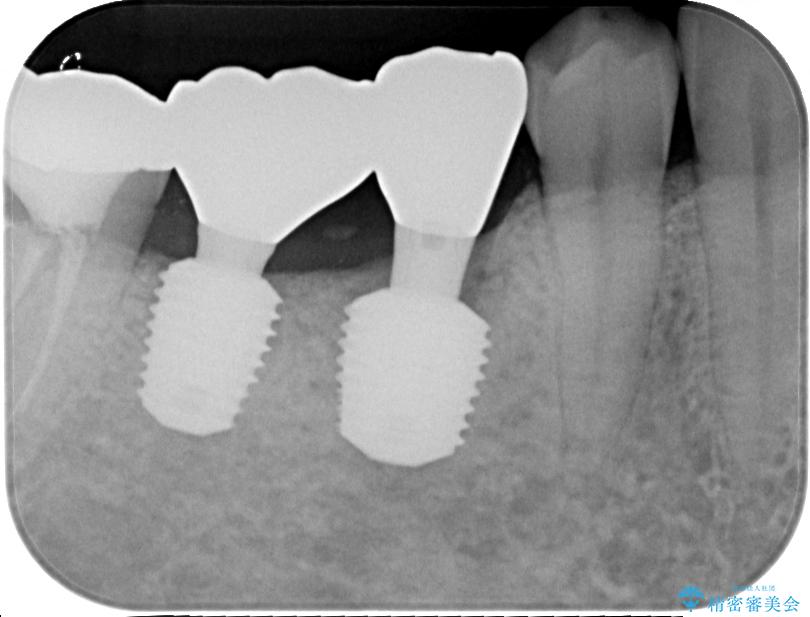

咬合力が非常に強い患者様であり、2歯欠損のブリッジ(しかも大臼歯は失活歯)は歯根破折のリスクが高すぎると判断し、抜歯部および欠損部に対して、インプラントによる補綴治療を行うこととしました。

抜歯即時埋入部と後方の欠損部は、即日荷重(インプラント埋入と同時に仮歯を装着すること)が可能な安定値が得られましたが、長い期間欠損した状態で過ごすと、欠損部に舌を押し当てる癖が発現してしまい、舌からの側方圧でインプラントが脱離するリスクが著しく高まってしまうため、即日荷重は行いませんでした。

おかげでインプラントは無事に生着し、僅か4ヶ月で治療を終えることができました。